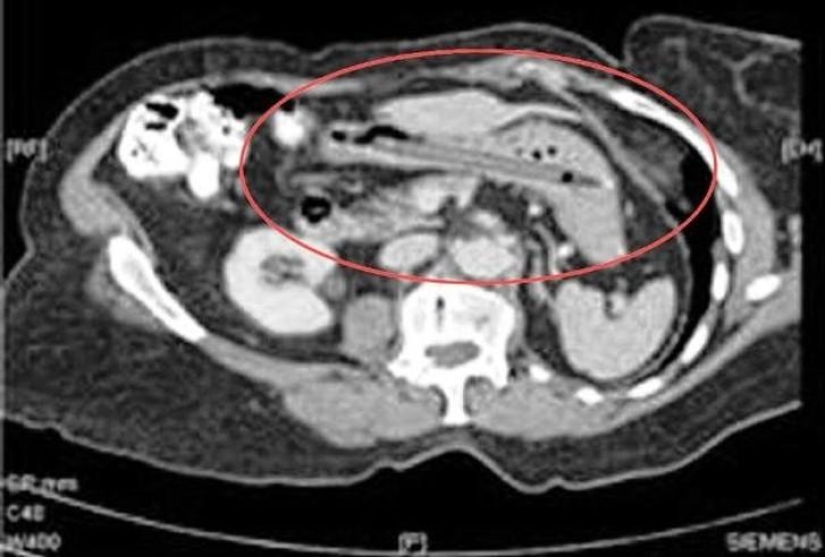

25. Live eel.